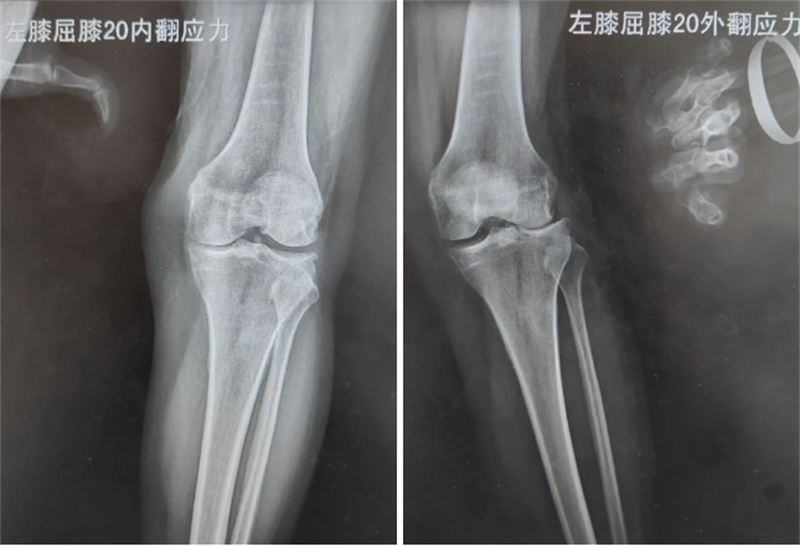

膝關(guān)節(jié)骨性關(guān)節(jié)炎是老年人膝關(guān)節(jié)疼痛的一大病因,困擾無(wú)數(shù)老年患者,59歲的徐女士就一直被該病困擾,出現(xiàn)膝關(guān)節(jié)疼痛、行走困難的情況。通過(guò)X線及磁共振檢查,醫(yī)生發(fā)現(xiàn)徐女士為膝關(guān)節(jié)外側(cè)盤(pán)狀半月板撕裂后局部常年受應(yīng)力刺激,關(guān)節(jié)外側(cè)軟骨磨損所致的膝關(guān)節(jié)外側(cè)間室骨性關(guān)節(jié)炎。考慮徐女士膝關(guān)節(jié)的韌帶及內(nèi)側(cè)間室軟骨完好,僅為膝關(guān)節(jié)外側(cè)間室的軟骨磨損,科室決定實(shí)施膝關(guān)節(jié)外側(cè)單髁關(guān)節(jié)置換術(shù),在解決徐女士膝關(guān)節(jié)疼痛的基礎(chǔ)上,盡可能減少正常膝關(guān)節(jié)結(jié)構(gòu)的損傷,實(shí)現(xiàn)術(shù)后快速康復(fù)、減少疼痛的目的。

醫(yī)生介紹,徐女士的這場(chǎng)手術(shù),能否精確完成術(shù)前設(shè)計(jì),恢復(fù)膝關(guān)節(jié)正常的關(guān)節(jié)線高度和下肢的力線是手術(shù)的重點(diǎn)。術(shù)前在手術(shù)機(jī)器人智能系統(tǒng)上根據(jù)患者下肢的CT測(cè)量數(shù)據(jù)進(jìn)行一系列的3D建模、數(shù)據(jù)分析、術(shù)前計(jì)算、術(shù)中計(jì)劃,最終確定假體的大小、截骨范圍、放置位置等。